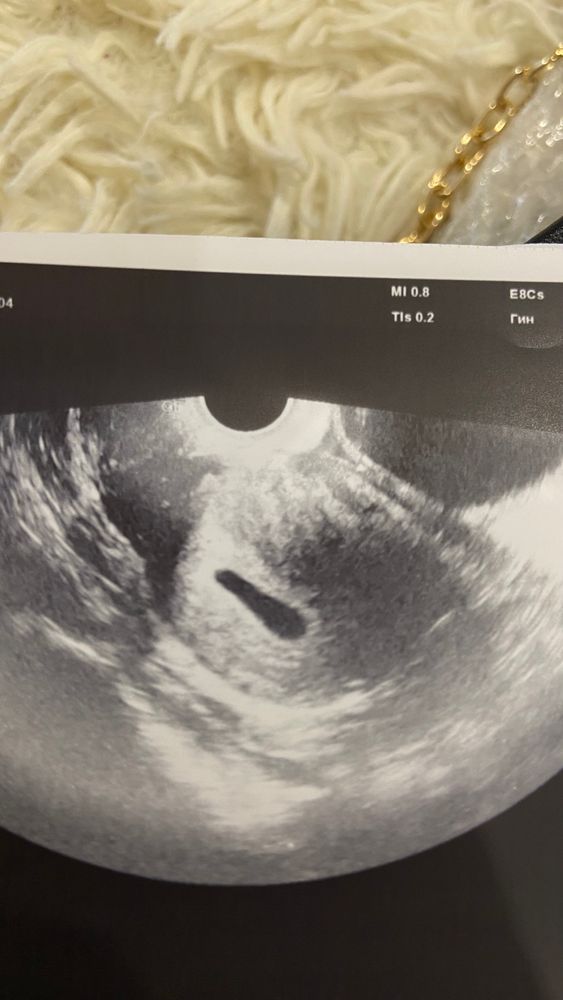

6 недель не видно эмбриона

Здравствуйте девочки расскажите было ли у кого такая ситуация что в 5-6 недель не видно эмбриона

У меня в 6 акушерских недель определили только плодное яйцо и желточный мешок. А через 1,5 недели (в 7+3) уже плод посмотрели.

Эмбриона ладно может быть не видно еще, рано, но у вас тут и жм не видно, ждите следующего узи и хгч обязательно должны было быть в динамике

Карина Москвичева, размер плодного яйца на 6 недель,но в 6 недель ктр уже должен быть,мне например с пустым пя 20 мм,5 недель ставили,так как не было эмбриона,был бы эмбрион,то не важно какое пя,ставят срок по его размерам,у вас 31.05 и было 6 акушерских (4 от зачатия) хгч 16.05 соответствует 13-14 дпо,значит 31.05 было 28-29 дпо,а это 4 недели от зачатия,а акушерский на две недели больше,т.е 6 должно быть,ладно эмбрион,но жм должен 100% быть,он уже в 3 недели от зачатия есть